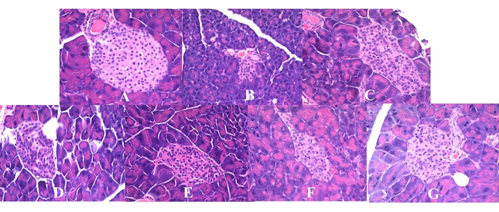

本研究将发酵好的酸奶按照不同剂量对2型糖尿病小鼠进行饮食干预,研究发现不同剂量的GABA酸奶在不同程度改善糖尿病相关指标,如增加血清胰岛素和脂肪指数、降低血液中尿素氮水平、减少葡萄糖曲线下面积和胰岛素敏感性指数等;其中,高剂量的GABA酸奶在改善胰岛素敏感性方面优于低剂量组,主要体现在HOMA-β、总胆固醇、高密度脂蛋白、脂肪指数和胰岛细胞形态等方面。这一工作为揭示富含GABA发酵食品的营养价值和新型功能性食品的开发利用提供了理论借鉴

图2 不同剂量GABA酸奶对胰腺形态的影响